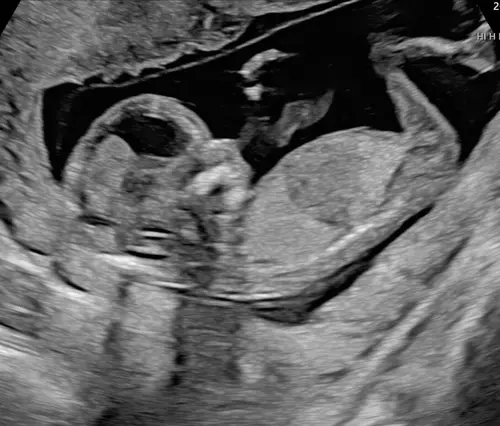

Iemand enig idee? 🫶🏼